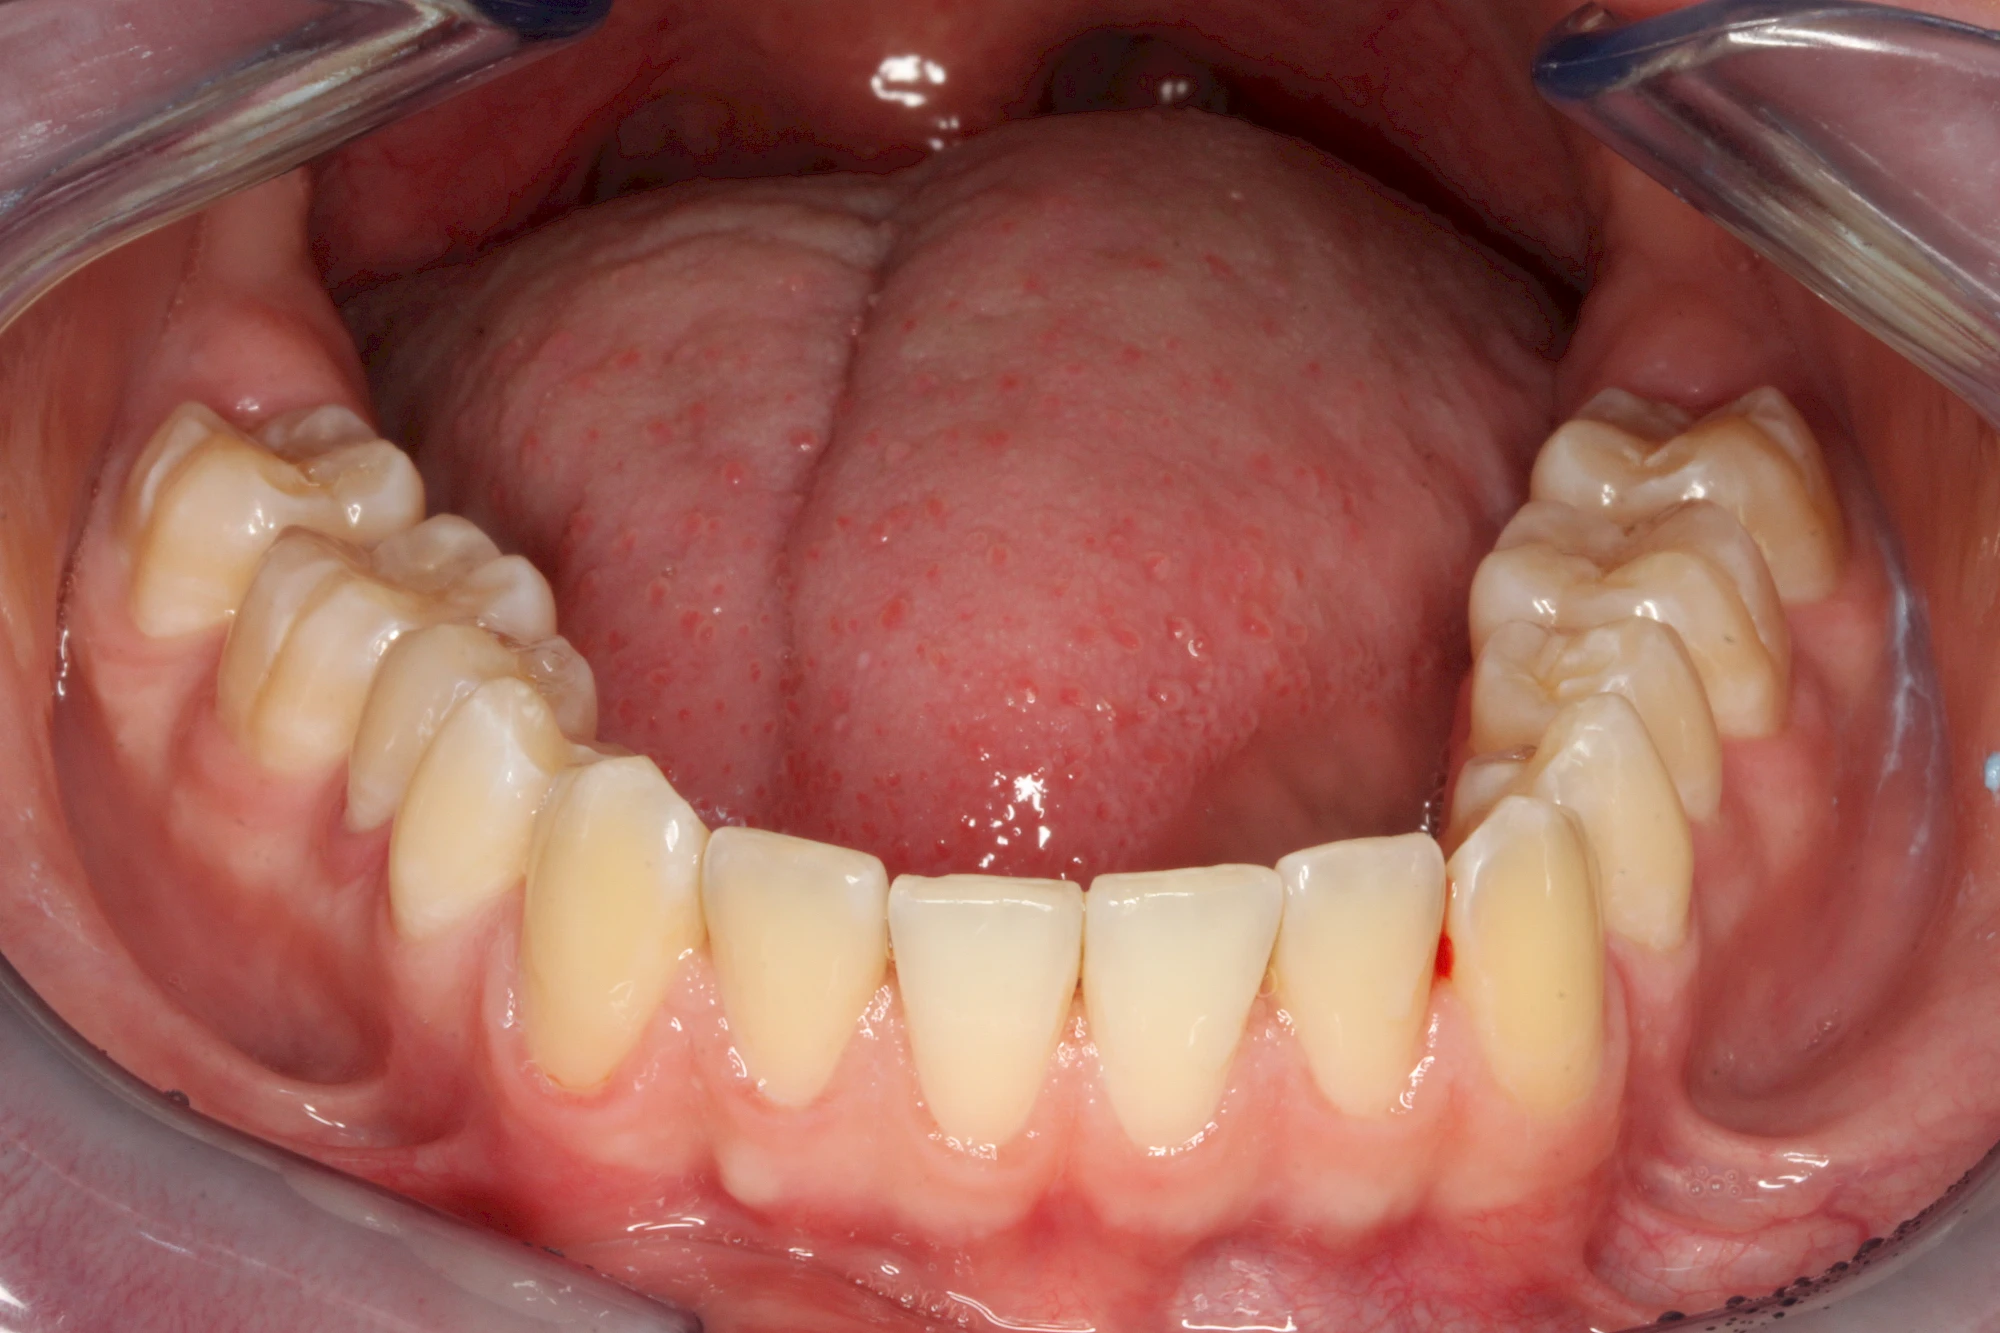

Von außen (exogen) eher dunkel gefärbt und meist mehrere Zähne betroffen:

- Genußmittel (Tee, Kaffee, Rauchen)

- Medikamente (z. B. Eisen)

Äußere Verfärbungen durch Genußmittel oder Medikamente (Eisen!) lassen sich meist nur durch den Zahnarzt z. B. mit einer professionellen Zahnreinigung entfernen.